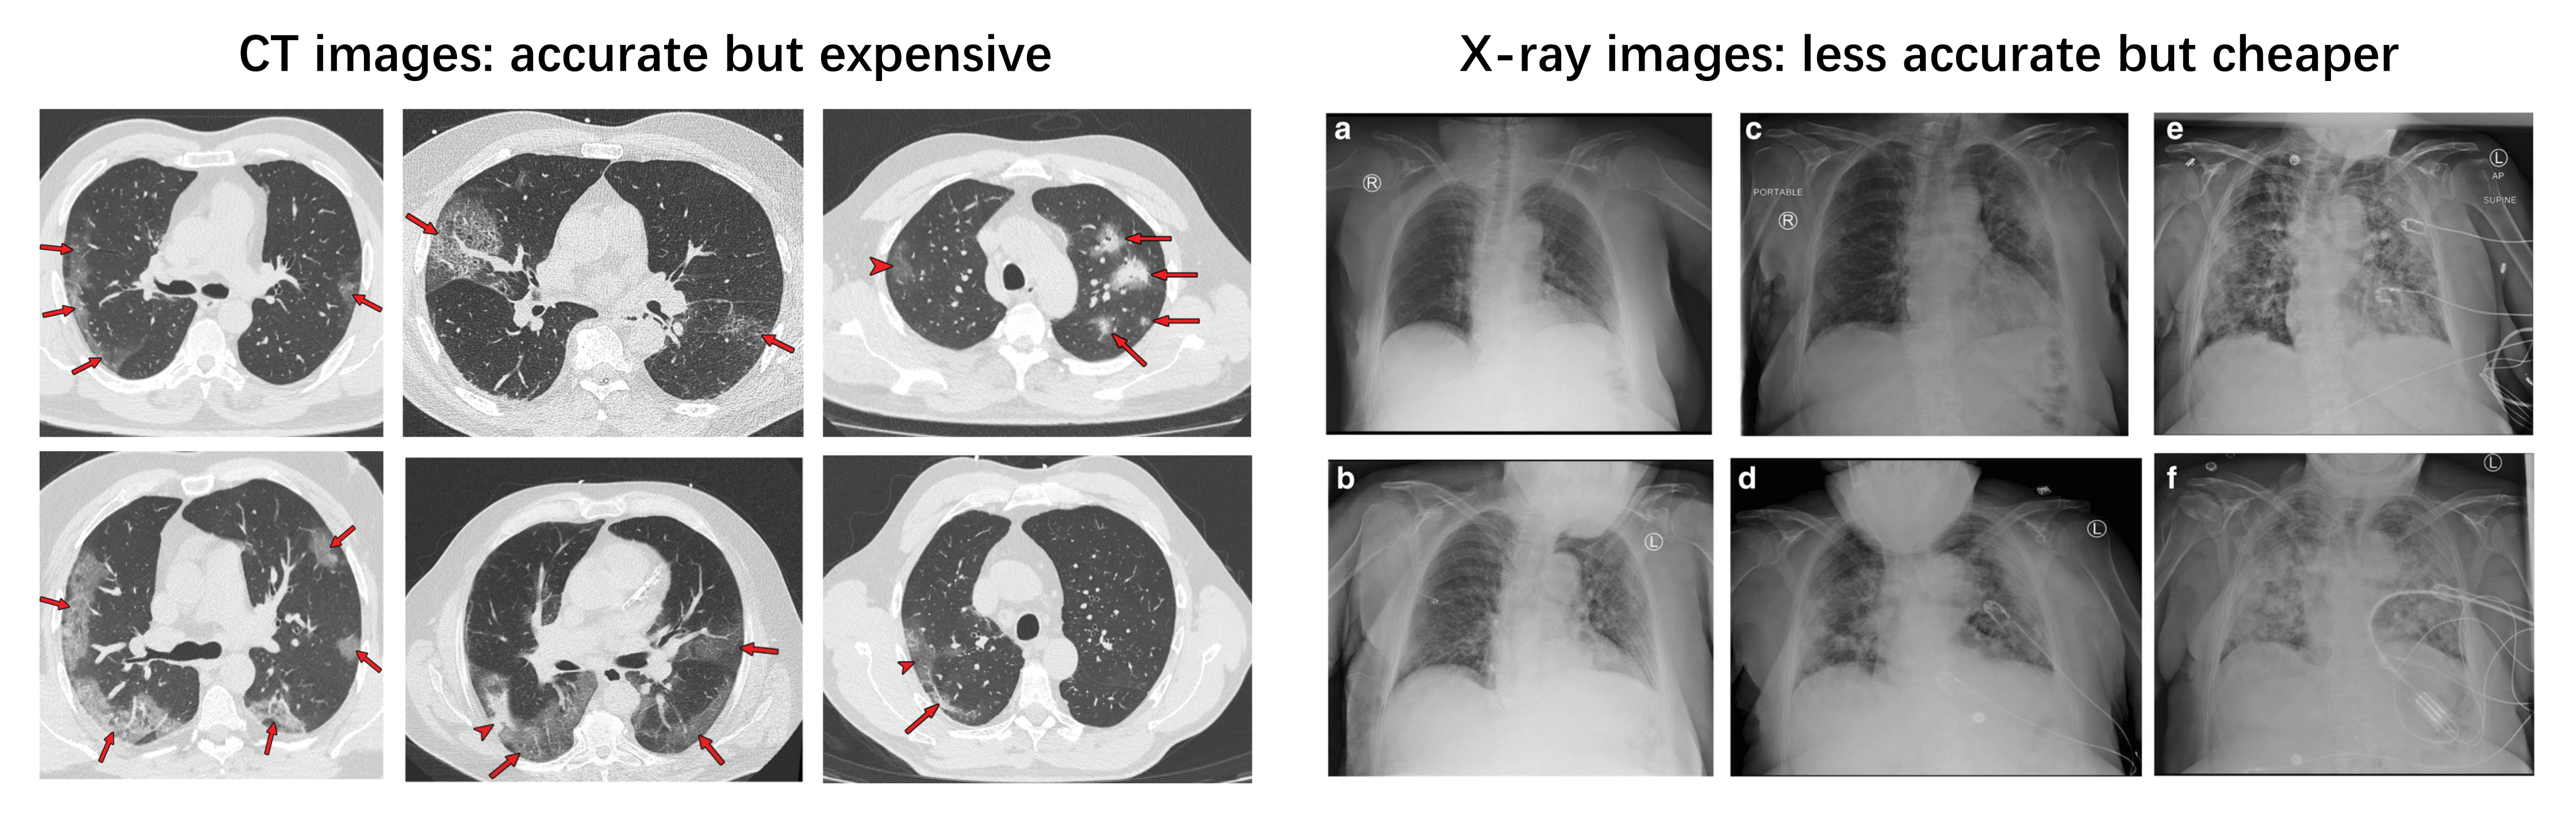

2. Input Modalities: CT or X-ray

2.1. Clinical Perspective

2.2. Artificial Intelligence Perspective